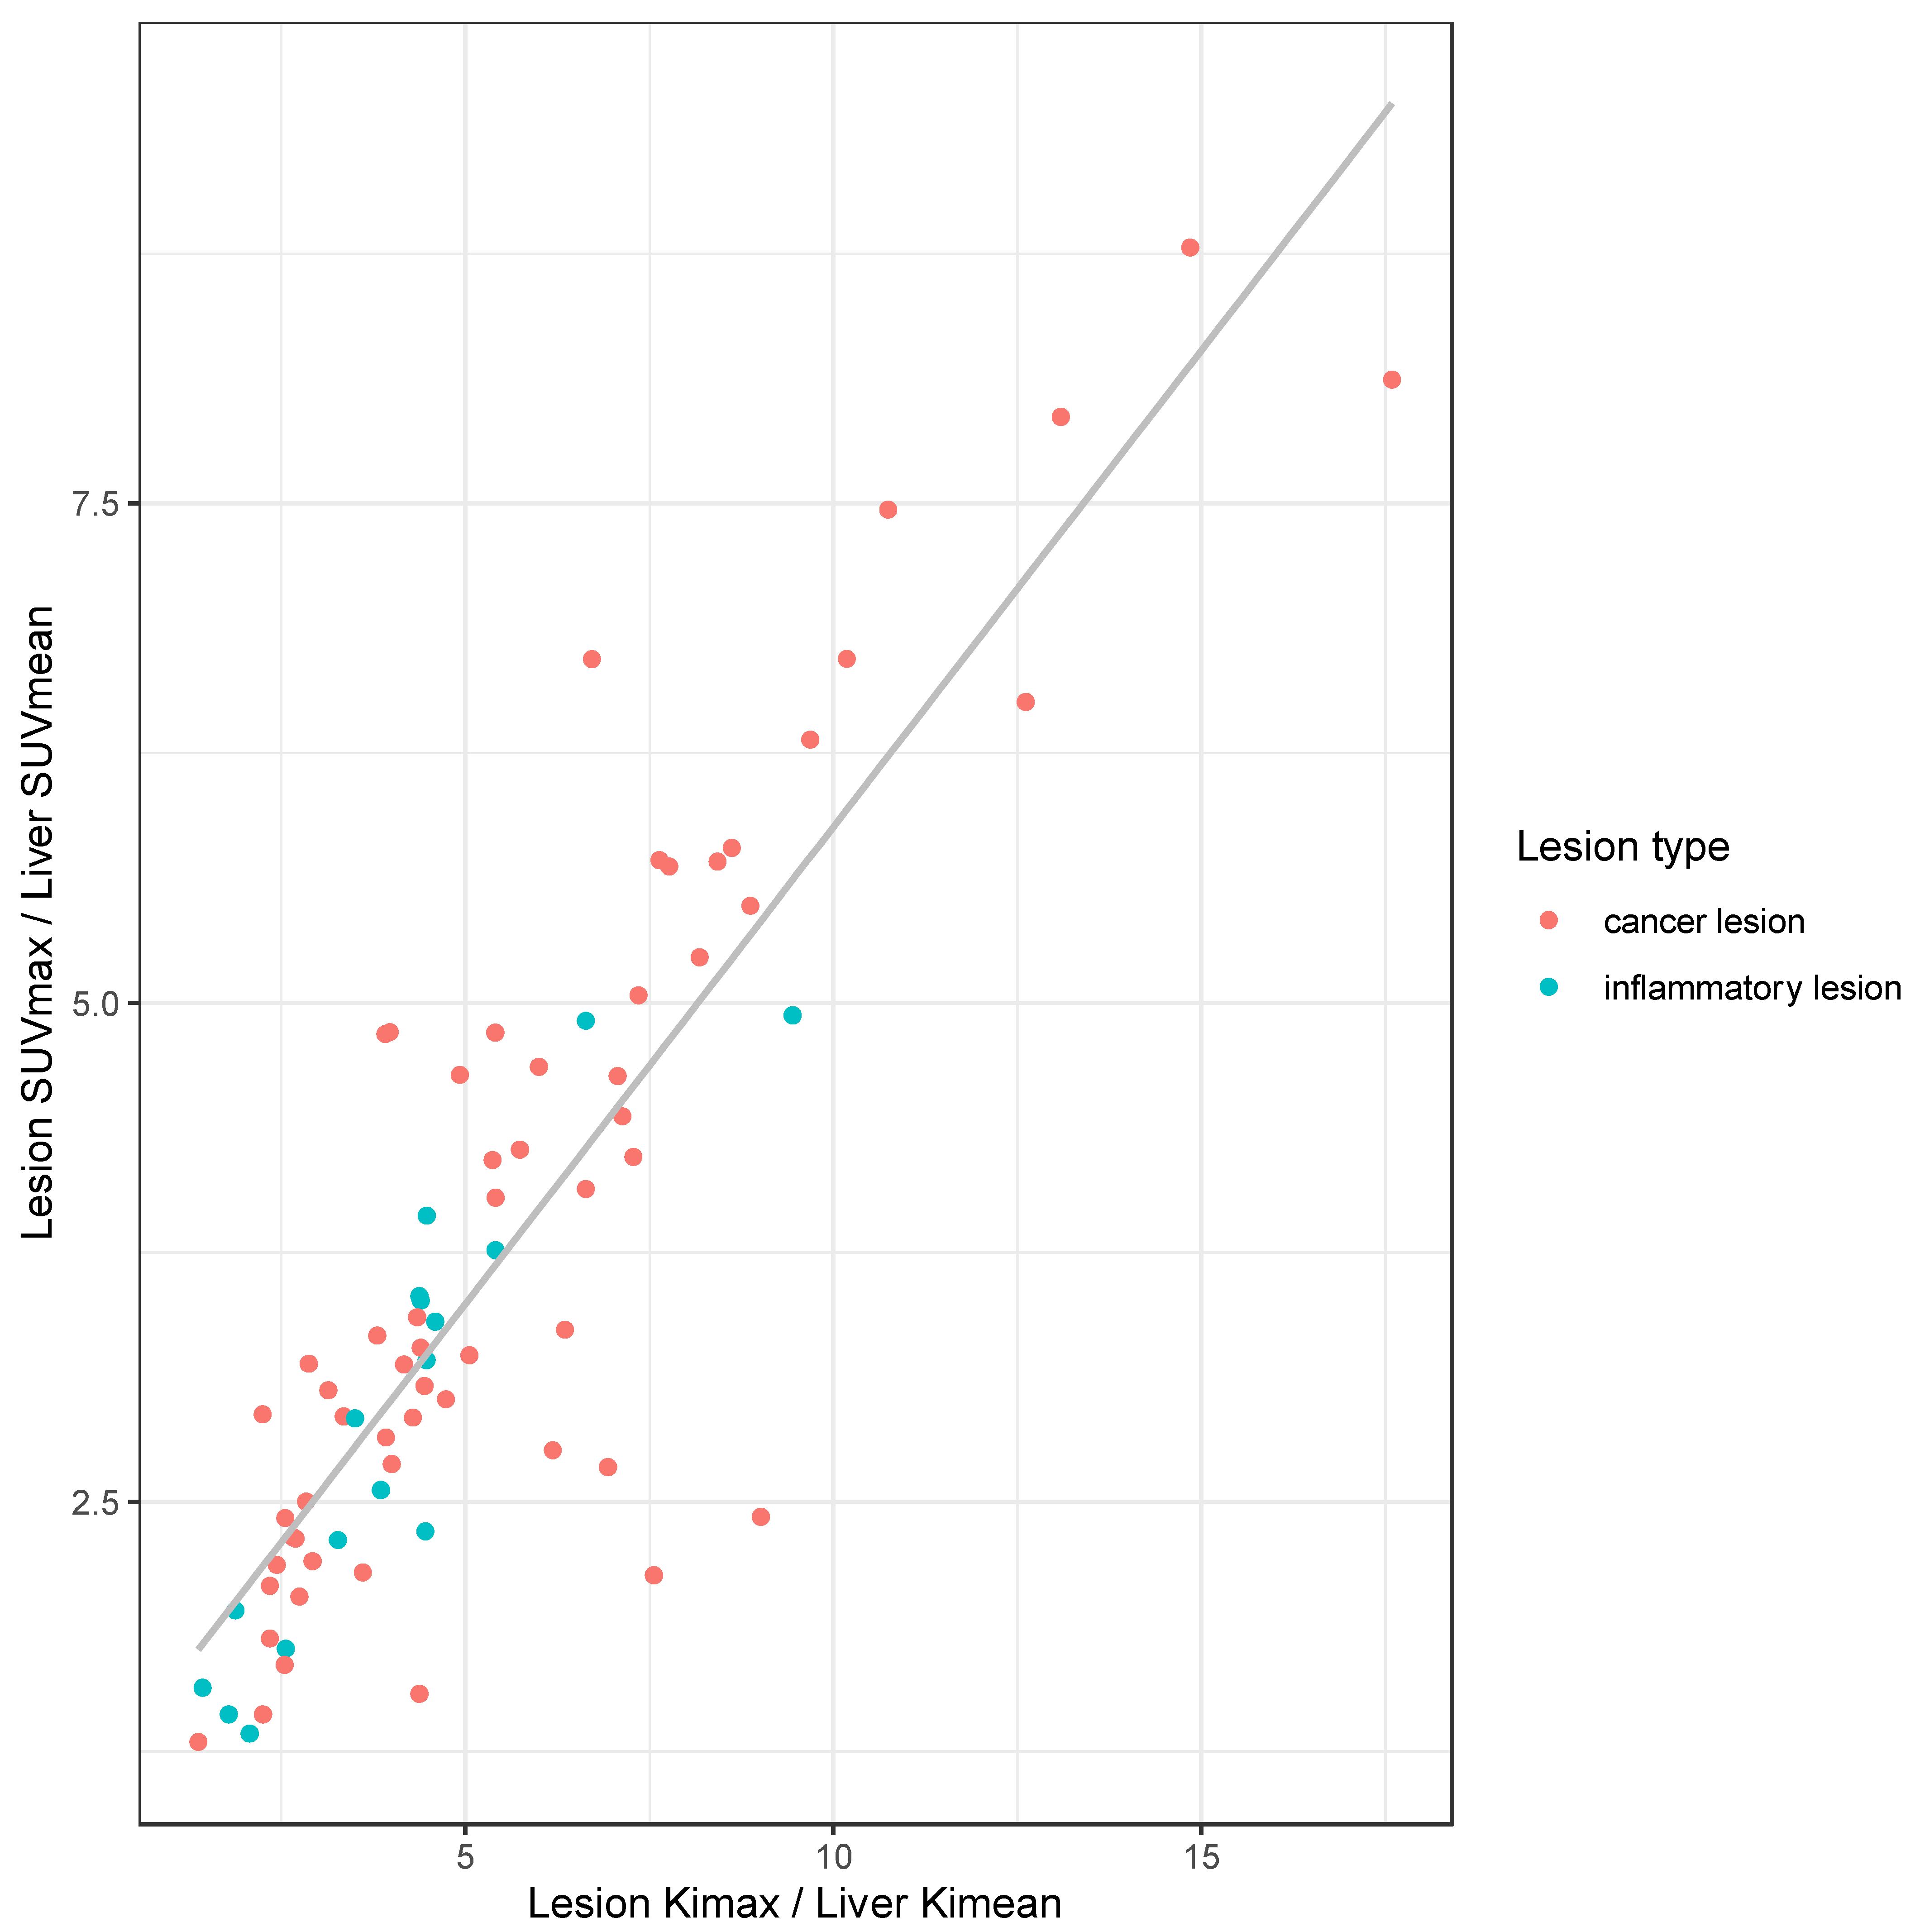

3.4. Differentiation of Malignant vs. Inflammatory Lesion in Clinical and Dynamic Imaging

4. Discussion